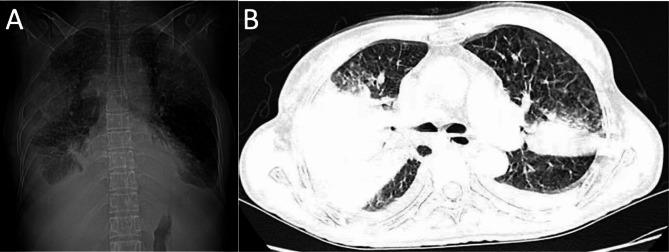

A 52-year-old woman presented with a fever, which has persisted for the past eight days, along with worsening shortness of breath and decreased blood pressure. Computed tomography (CT) revealed an air bronchogram, lung consolidation, and bilateral pleural effusion. The subsequent polymerase chain reaction (PCR) of the bronchoalveolar lavage fluid (BALF) revealed positivity for H5N1 and severe acute respiratory syndrome coronavirus 2 (SARS-CoV-2).

一名 52 岁女性因发热持续 8 天,伴呼吸困难加重和血压下降而就诊。计算机断层扫描(CT)显示空气支气管征、肺部实变和双侧胸腔积液。随后对支气管肺泡灌洗液(BALF)的聚合酶链反应(PCR)显示 H5N1 和严重急性呼吸综合征冠状病毒 2(SARS-CoV-2)均呈阳性。